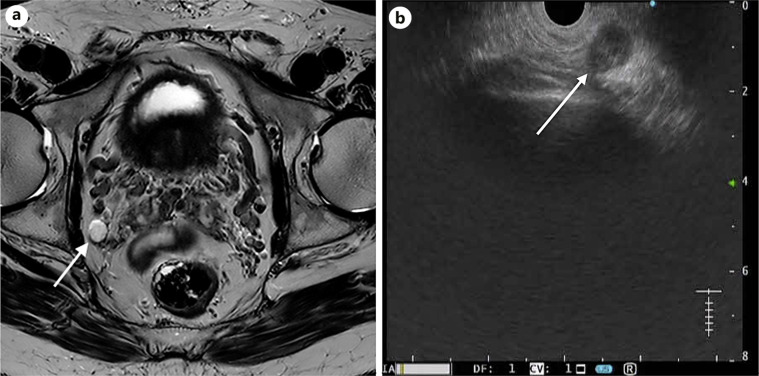

Case presentations: We report 8 cases of suspected locoregional tumor growth (LRTG) on MRI: adjacent or in the rectal wall, within the mesorectal fascia, high presacral region, and obturator foramen. MRI images were studied thoroughly before and during EUS to identify the target lesion using rectal EUS-FNA. Patients were prepared using an enema. The procedure was performed on an outpatient basis without conscious sedation. FNA was performed using a 25G needle. The patient received a 3-day course of ciprofloxacin after the procedure to prevent infection of the perirectal space. Identification of the target was the most difficult part of EUS but was successful in all cases. FNA revealed adenocarcinoma in 7 cases. Five cases were confirmed by TME results: 1 patient died before the operation, and 1 patient was treated with CRT. One patient with a suspected node in the obturator foramen was free of tumors on FNA. The TME resection specimen contained 31 lymph nodes without metastasis. All procedures were well tolerated, and no complications were observed.

Abstract Image